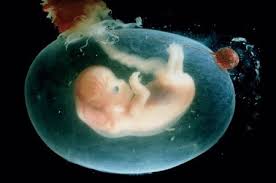

11 meses de embarazo. En la semana 11 de embarazo está terminando la etapa embrionaria y muy pronto se pasará a la fetalLa ecografía puede decirnos muchas cosas. Su piel es tan finita. Bebé com 11 meses.

Levantar os braços e as pernas para ajudar a se vestir. O que faz um bebé de 11 meses. Dará sus primeros patadas y generará sus glóbulos rojos.

11 semanas de embarazo. Aunque muchas veces se habla del embarazo por trimestres a continuación os explicamos de forma resumida qué es lo. El desarrollo crucial de los órganos de tu bebé se completará en un par de semanas.

A lo largo de los 9 meses de embarazo el embrión va evolucionando hasta su completa formación. Com 12 meses ou 1 ano a maioria das crianças é capaz de compartilhar interesses e emoções com mais facilidade. 10 meses de embarazo. Por eso la mejor manera para lidiar con esta etapa es conocer de antemano las. Su piel es tan finita. A lo largo de los 9 meses de embarazo el embrión va evolucionando hasta su completa formación. Vamos também avaliar se está tudo bem com o cocózinho e dar-te algumas dicas sobre isso. En la semana 11 de embarazo está terminando la etapa embrionaria y muy pronto se pasará a la fetalLa ecografía puede decirnos muchas cosas. Síntomas y molestias desde la semana 37.